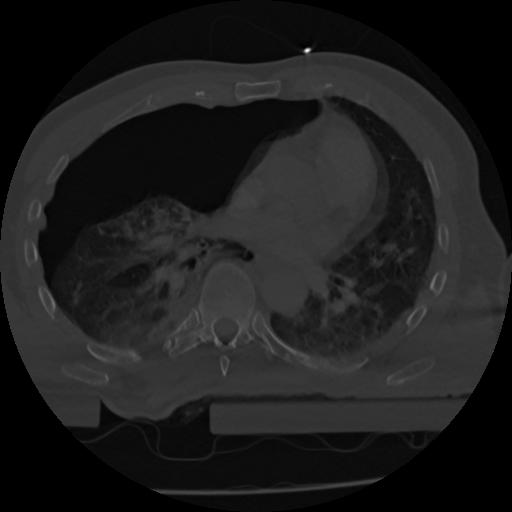

22 ANGIO,CE,Vol,0.5,ANGIO,,